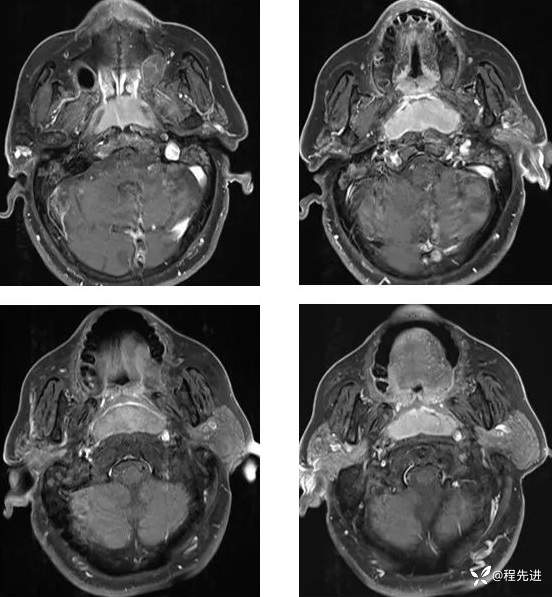

T1增强: